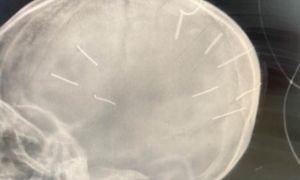

Kết quả phim chụp X-quang cho thấy, bé Đ.N.A., 3 tuổi, ở Canh Nậu, Thạch Thất, Hà Nội có đinh trong sọ, tiên lượng tử vong cao.